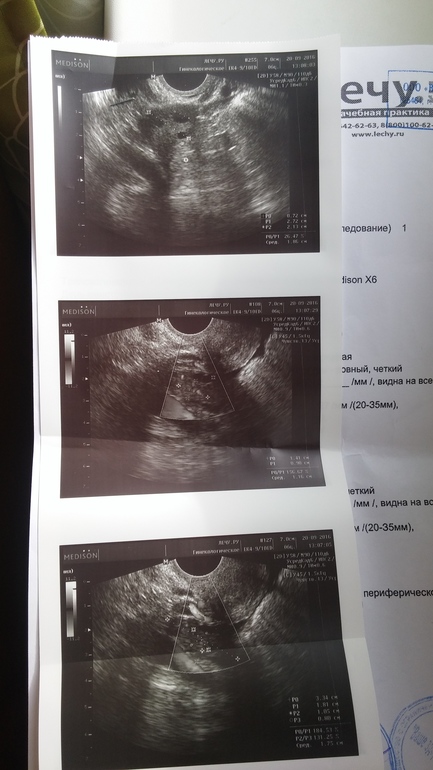

Фолликулометрия. Результат :

Овуляция( тесты на овуляцию)Девочки,сходила я значит на фолликулометрию и чет расстроилась...О подтвердили. Предыстория : сегодня у меня 25ДЦ и 5ДПО. Все в норме,жт есть,но его немного! Врач сказал сдать кровь на прогик-уже сдала,завтра заберу результаты. Теперь я так переживаю,что проблемы с прогиком и пролет в этом месяце...единственно что врач сказал,что ДПО прошло немного и возможно из-за этого жт нет в нужном кол-ве. Девочки,поддержите ((((неужели это пролет...p.s анализы (под кат)

подожди расстраиваться!!!!все хорошо-еще не понятно.жт можно подрастить с помощью дюфа.....если прогик не обнадежит да и детке есть где крепиться ...правда не вижу эндометрий какой